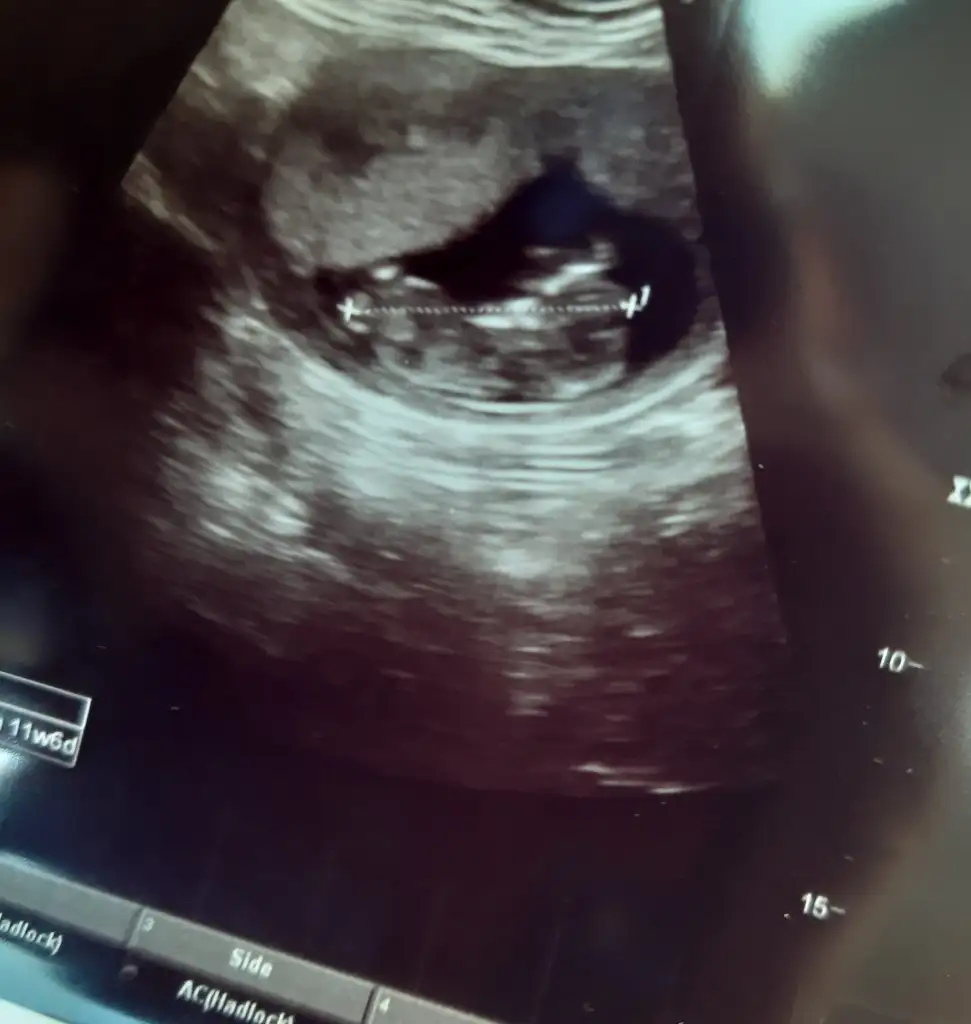

Bana da rica etsem bakar mısınız 11 haftalik usg göre 11+6 gözüküyorDönüş yaparsanız sevinirim

Kız13+0 haftalık olduk bize de lütfen yorum yaparmısınız

Erkek gibi sanki13+0 haftalık olduk bize de lütfen yorum yaparmısınız

Erkek gibi görünen yeri bana gösterebilirmisin canım zahmet olmazsa. Ben o kadar baktım anlamadım açıkçasıErkek gibi sanki

Erkek gibi görünen yeri bana gösterebilirmisin canım zahmet olmazsa. Ben o kadar baktım anlamadım açıkçası